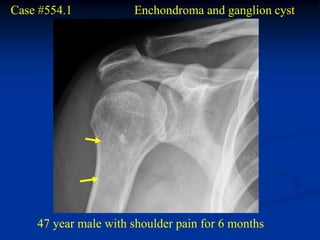

Case #554.1           Enchondroma and ganglion cyst

47 year male with shoulder pain for 6 months

ganglion

enchondroma                cyst

Coronal T-2 MRI

Sagittal T-2 enchondroma   Sagittal T-2 ganglion

Two different T-2 axial cuts showing the enchondroma

and the right cut shows the ganglion